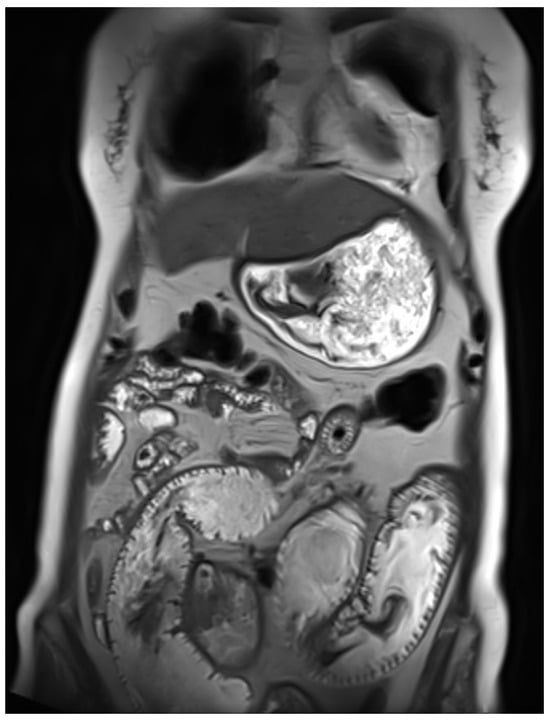

At the time of consultation in our department, the patient’s general health status and biological parameters were excellent. Although the surgery had cytoreductive intent, the postoperative MRI detected residual disease (peri centimetric peritoneal and hepatic metastases)—confirmed by postoperative MRI (see Figure 3). T2W heterogeneous lesions displaying restricted diffusion are observed. These lesions measure 18 × 14 mm on peritoneal surface at the level of liver segments 8–4, 22 × 8 mm and 25 × 10 mm adjacent to each other at the level of segment 2 and 20 × 9 mm adjacent to surgical site on peritoneal surface at the level of segment 6. The patient had a good performance status, no comorbidities, and no contraindications to combined immune-targeted therapy. After multidisciplinary discussion, we opted for treatment with a MET kinase inhibitor (cabozantinib) in combination with a PD-1 checkpoint inhibitor, based on its more favourable safety profile compared to other VEGFR inhibitors such as pazopanib or sunitinib [21]. Furthermore, the NGS panel from the cytoreductive surgery identified PD-L1 expression at 15% TPS, with variants of unknown significance (VUS) in MYC, EWSR1, and STAG2. Given the patient’s prior intolerance and lack of benefit from chemotherapy, first-line targeted therapy combined with immunotherapy was considered a rational and potentially more effective therapeutic option. The combination of cabozantinib, a multi-target tyrosine kinase inhibitor with activity against MET, VEGFR, and AXL, and nivolumab, an immune checkpoint inhibitor targeting PD-1, was selected based on their potential synergistic effect. Cabozantinib may enhance antitumor immunity by modifying the tumour microenvironment, reducing immunosuppressive signalling, and promoting T-cell infiltration, thereby potentiating the efficacy of PD-1 blockade. Although prospective evidence in GNET/CCS is lacking, emerging data in other sarcomas and rare tumours support this strategy as a rational approach in the absence of standard treatment options.

Figure 3. Liver and peritoneal metastases on MRI post-cito-reductive surgery.